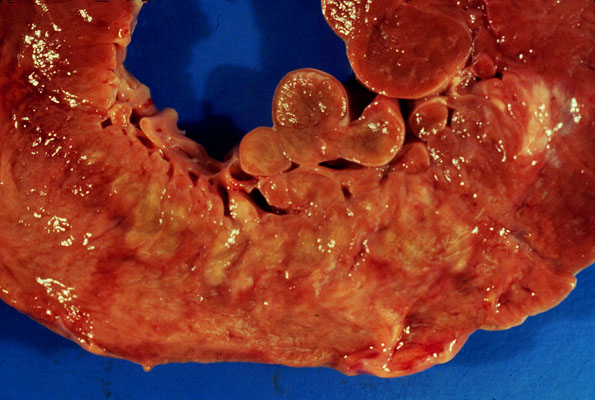

MI, gross

Acute

myocardial infarct

. This 3-4 day old infarct appears yellow.